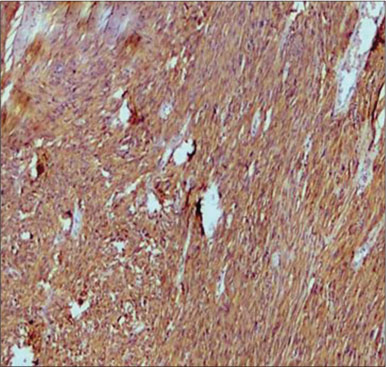

A total of 90 mesenchymal tumors of the GIT and pancreas diagnosed in SKIMS from January 2010 to December 2016 were reclassified on the basis of morphologic features and IHC into 77 (85.6%) cases of GIST and the remaining 13 (14.4%) cases as other mesenchymal tumors. The mesenchymal tumors included five cases of inflammatory myofibroblastic tumors, two cases of leiomyoma, four cases were sarcomas, one case was poorly differentiated carcinoma, and one was desmoid tumor. C-KIT positivity was seen in 72 (93.5%) cases and DOG 1 was positive in 77 (100%) cases [Figures 1], [2], [3], [4]. However, the correlation between DOG1 and CKIT was found to be statistically insignificant (P = 0.23). There was no significant association between DOG 1 expression and various histopathological parameters in the studied cases. Clinicopathological variables have been enumerated in [Table 1].

| Figure 3 CKIT staining